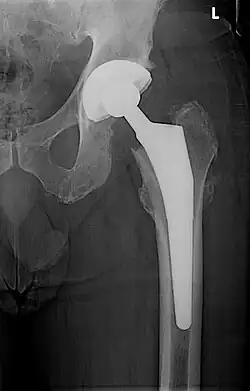

Kunstheup

Een kunstheup bestaat uit meerdere componenten; een steel die in het bovenbeen wordt geplaatst en een cup (kom) die in het bekken wordt geplaatst. Op de steel kan een kopje geplaatst worden door middel van een conisch toelopend eind. Het kopje wordt hierop vastgeslagen. er ontstaat dan een koudlas. De doorsnede van dit kopje bedraagt in het algemeen 28 mm. Om het verschil in doorsnede tussen de kom, die vaak minimaal 46 mm is te overbruggen moet in de kom een laag polyethyleen worden aangebracht. Bij gecementeerde heupprothesen is dit niet nodig, zie hieronder.

Een kunstheup gaat in het algemeen zo'n vijftien jaar mee. In de meeste gevallen laat de kunstheup na een dergelijke periode los en ontstaat botverlies. Hierdoor ontstaat pijn en verzwakt het bot. Dit is een reden om de heup te vervangen, hetgeen een grotere ingreep is dan het plaatsen van een prothese als het de eerste keer betreft. Er kan ook slijtage optreden ter hoogte van het contactvlak tussen kopje en kom. Door de losgelaten deeltjes reageert het lichaam met afstotingsverschijnselen waardoor de heup loslaat.

Er bestaat een onderscheid tussen gecementeerde en ongecementeerde heupprothesen. Gecementeerde heupprothesen worden geplaatst door een polymeer, polymethylacrylaat, te gebruiken, dat vergelijkbaar is met tweecomponentenlijm. Deze methode werd al door Charnley gebruikt en is heden ten dage nog de standaard.

Ongecementeerde heupprothesen zijn gemaakt van titanium, een lichaamsvriendelijk metaal. Hierbij wordt geen cement gebruikt maar wordt de prothese zo passend mogelijk in het bot geplaatst nadat dit op maat is gebracht. Het oppervlak van een dergelijke prothese is ruw waardoor het bot de gelegenheid krijgt zich hierop te hechten.

Er zijn meer verschillen in materiaal bij gecementeerde en ongecementeerde heupprothesen. De kom bestaat bij een gecementeerde heup uit polyethyleen en de steel en de kop uit een legering: chroom, kobalt en molybdeen. Bij een ongecementeerde heup bestaat zowel de kom als de steel uit titanium. Het contactvlak tussen kop en kom bestaat in de meeste gevallen uit metaal en polyethyleen. De laatste jaren is metaal op metaal in opkomst. Er komt steeds meer bewijs dat deze methodiek minder slijtage tot gevolg heeft. Langetermijnresultaten ontbreken vooralsnog.